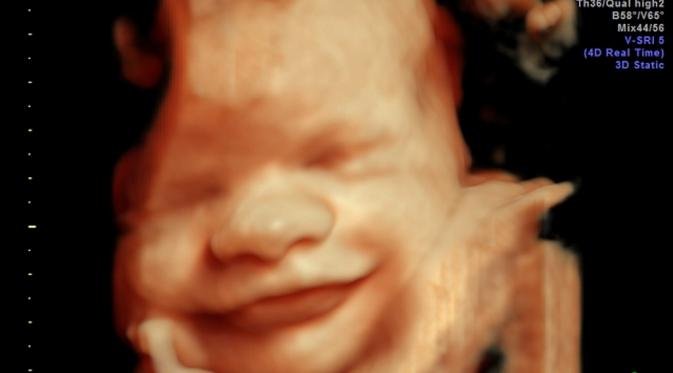

Perbedaan USG 2D, USG 3D, dan USG 4D: Memahami Teknologi Pemindaian Janin

USG Apa yang Lebih Unggul? Ini Penjelasannya